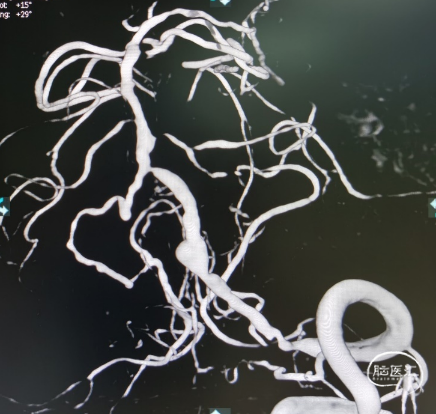

左侧椎动脉V4段狭窄,远端见瘤样扩张;右侧椎动脉闭塞。脑血管符合硬化表现。(阅片)

造影提示右侧椎动脉闭塞,左侧椎动脉V4多发重度狭窄,并V4段夹层动脉瘤

Transcend携带SL-10微导丝进入左侧大脑后动脉,明确真腔内后交换Gateway2.0mm×15mm以命名压缓慢进行两次扩张,造影见现在较前改善,动脉瘤近端存在狭窄暂时未扩张